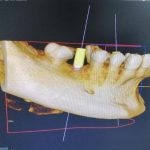

Tras realizar la valoración pertinente, le tomamos al paciente un registro en 3D Tac Dental (CBCT) con la finalidad de analizar y programar al detalle la colocación de los implantes. Es un paso necesario previo al comienzo del tratamiento, que nos ayuda a planificar los pasos a seguir y a determinar los plazos.